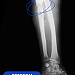

-В первую очередь нам необходимо было справиться с инфекцией. При свищевом остеомиелите ждать результата от обычной антибактериальной терапии бессмысленно. Воспалительный процесс разрушил кость на участке длиной 8 сантиметров. Этот фрагмент подлежал удалению в пределах здоровых тканей. На его место установили спейсер из антибиотика и костного цемента. Мы изготовили его самостоятельно в условиях операционной, по собственной технологии и индивидуальным размерам. Имплантат выполнял двойную задачу. Во-первых, это источник антибиотика в непосредственном очаге заражения. Во-вторых,- механическая поддержка для кости за счёт своей армирующей функции, - объясняет Сергей Глиняный.